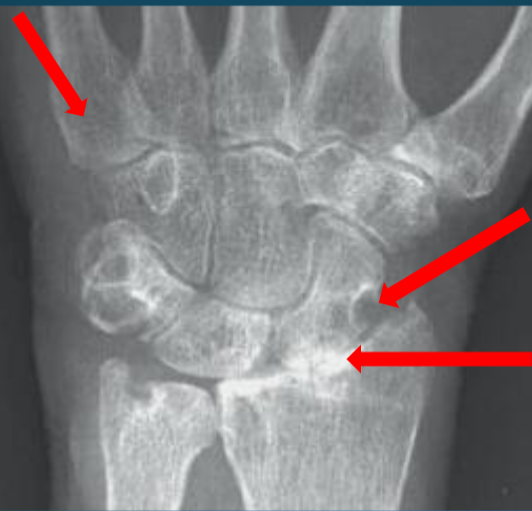

Rheumatoid Arthritis

periarticular osteopenia

erosions

joint space narrowing

Psoriatic Arthritis

DIP Involvement → Pencil in Cup Deformity